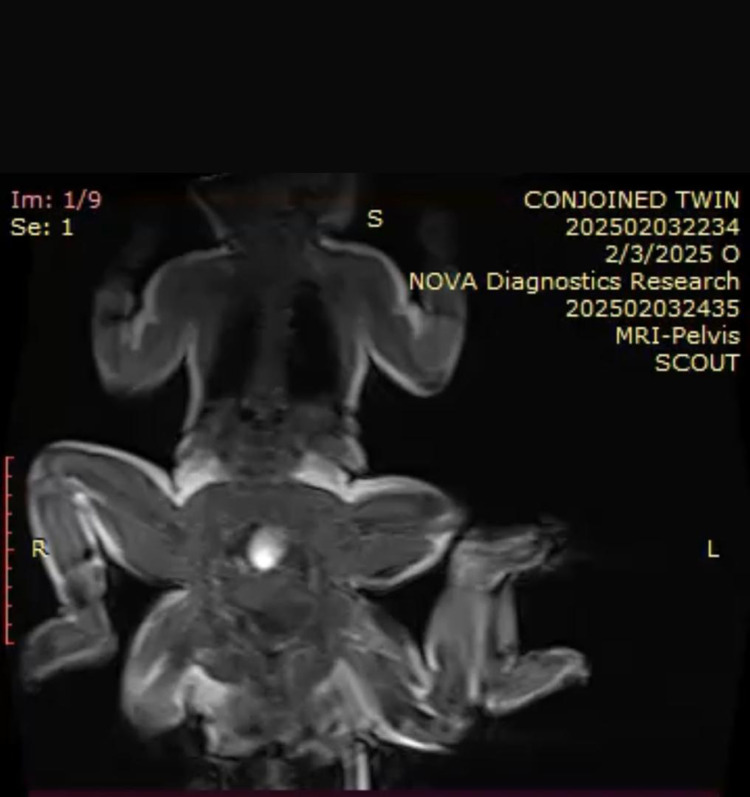

Background: The birth of conjoined twins is an extremely rare neonatal condition, occurring in approximately 1 in 100,000 live births. Ischiopagus, a form of conjoined twinning where the twins are joined at the pelvis, accounts for 6-11% of all conjoined twins. Ischiopagus conjoined twinning is a congenital anomaly. The surgical separation of conjoined twins is challenging due to the intricate anatomy and physiology involved. Thorough preoperative evaluation, meticulous planning, and a skilled surgical team are essential for ensuring a successful outcome. This condition significantly requires separation surgeries due to the unique anatomical challenges it presents. Clinical outcomes can vary depending on the healthcare facility and resources available. The development of conjoined twins consistently draws significant attention from researchers and clinicians. Aside from the rarity of such cases, the manner in which these twins develop remains a topic of ongoing debate. This report describes a case of ischiopagus conjoined twins, characterized by two heads (dicephalus), four upper limbs (tetrabrachius), and a shared pelvis with single umbilical cord. The mother of the twins was referred from a primary hospital Somali Sudanese Specialized Hospital for specialized care during her twin pregnancy, where a cesarean section was performed.

Case summary: The twins delivered by 34 years old gravida 9 para 7, no previous congenital anomalies, the mother was diabetic and she was on anti-diabetic drugs. Both parents had no family history of birth defects or exposure to known teratogens. Imaging (MRI) revealed that that the twins had separate hearts, lungs, kidneys with severe hydronephrosis in one of them, stomach, liver, spleen, and anal canals but shared the bowel loops, a single placenta with one umbilical vein and two umbilical arteries with single umbilical cord. Additionally, they have uterus-like structure with the absence of external genitalia. Despite multiple associated cardiovascular anomalies, there were no external craniofacial, limb, or brain abnormalities. The twins admitted for the neonatal ICU and observed with normal meconium and urinary passage from same opening (cloaca).